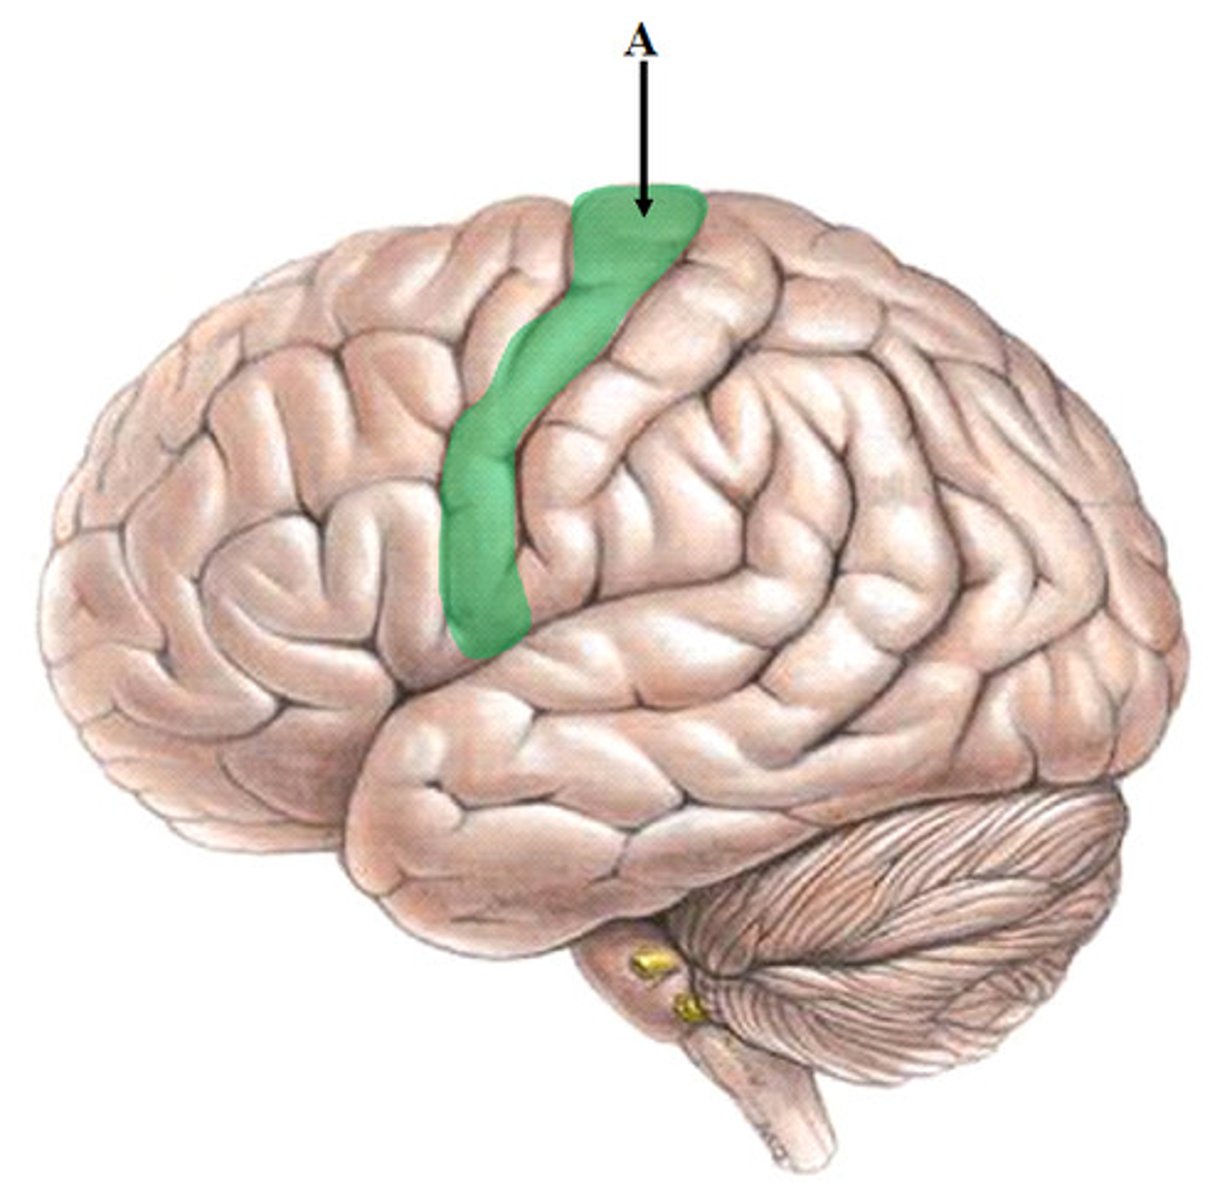

precentral Gyrus

pre-central gyrus